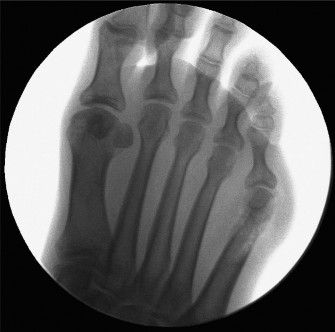

The correct answer is (B). This scenario describes a patient with a type III bunionette. Type III bunionettes are characterized by an increase in the IMA >8 degrees and can be effectively treated with a diaphyseal osteotomy (Fig. 5–82). Type I bunionettes have a normal 4–5 intermetatarsal angle (6.5–8 degrees) and an enlarged metatarsal head. Type II bunionettes are characterized by a lateral bow (outward curvature) in the fifth metatarsal shaft, resulting in a prominence over the metatarsal head, with a normal IMA.

Figure 5–82 Intraoperative image demonstrating correction of the 4–5 IMA using a diaphyseal osteotomy and bioabsorbable fixation.